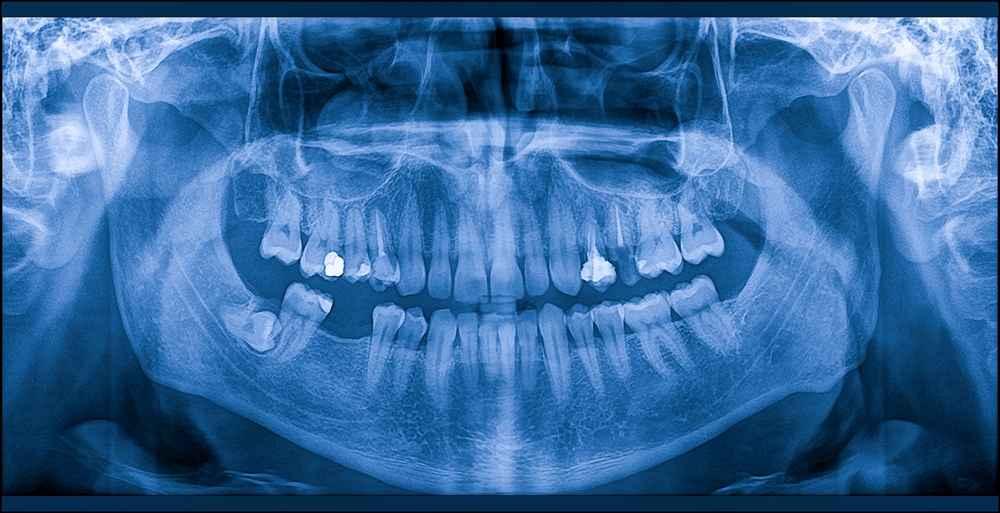

Erupsi gigi adalah serangkaian proses pertumbuhan dan perkembangan gigi di dalam rahang sampai akhirnya muncul di rongga mulut dan berfungsi sebagaimana mestinya.

Sederhananya, erupsi gigi adalah proses ketika gigi muncul dari dalam gusi. Pada manusia, erupsi gigi terbagi menjadi dua proses.

Proses pertama adalah erupsi gigi susu yang yang dimulai ketika anak-anak berusia sekitar enam bulan.

Setelah itu, gigi permanen akan mulai muncul ke permukaan gusi ketika anak-anak berusia sekitar enam tahun sampai remaja.

Mengutip dari laman National Health Services, gigi susu yang pertama kali muncul biasanya adalah gigi seri bawah (gigi depan).

Umumnya, anak-anak akan memiliki gigi susu lengkap sebanyak 20 buah saat berusia 2–3 tahun. Setelah itu, gigi permanen akan mulai erupsi ketika anak-anak berusia 6–7 tahun.

Urutan erupsi gigi permanen biasanya dimulai dari gigi molar (geraham) di rahang bawah dan diakhiri dengan gigi bungsu. Jumlah gigi permanen pada orang dewasa adalah 32.

Perbedaan jumlah gigi susu dan permanen tidak akan mengganggu Anda karena sejalan dengan pertumbuhan rahang.